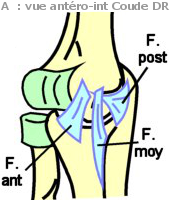

-

(Schéma

B) Le ligament collatéral radial

(old. lig. lat. interne ou LLE),

moins résistant que le précédent, irradie de la face antérieure de

l'épicondyle latéral en 3 faisceaux (F. Antérieur jusqu'au bord

antérieur de l'incisure radiale / F. Moyen jusqu'au bord postérieur de

l'incisure radiale / F. Postérieur se termine sur l'olécrâne).

(Schéma

B) Le ligament collatéral radial

(old. lig. lat. interne ou LLE),

moins résistant que le précédent, irradie de la face antérieure de

l'épicondyle latéral en 3 faisceaux (F. Antérieur jusqu'au bord

antérieur de l'incisure radiale / F. Moyen jusqu'au bord postérieur de

l'incisure radiale / F. Postérieur se termine sur l'olécrâne).

- Le ligament annulaire (à la fois surface articulaire et moyen

d'union) est un prolongement de la capsule, il s'enroule autour du

pourtour de la tête radiale. Sa face interne encroûtée de cartilage

est une surface articulaire. Il est plus large en HT qu'en BAS et

empêche la luxation lors de traction du radius vers le bas. Il est

tendu du bord postérieur de l'incisure radiale à son bord antérieur en

contournant le radius.